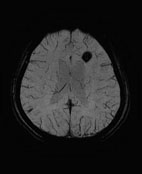

以往要完成所有全身磁振造影檢查的項目,最大的問題在於耗費的時間很長,即使再健康的人也無法忍受連續躺著三、四個小時做檢查。有鑑於此,本院健康管理中心特別耗資自?國引進全球最新、最快速全身磁振掃描儀器,將來一個半小時內即可完成高階全身健檢造影。不但如此,影像最高的解析度達到9μm,可以輕易地檢查出3mm甚至更小的腫瘤。另外,最新的平行造影技術,在短短幾分鐘內就可以提供腦部、內耳、脊椎、骨盆腔及膽道3D高解析度影像。這套系統另一項特點是SWI影像,它對於去氧血紅素及其它血液生成物有獨特的敏感度,不需要注射顯影劑,就能精確地顯示腦部微小的出血點、海綿狀血管瘤和動靜脈畸形異常結構...等,利用SWI能對於腦部事故傷害提供更精密的評估。

最新的SWI影像,能精確地顯示腦部微小的靜脈血管結構,圖中?色的病灶是一個出血的血管瘤。